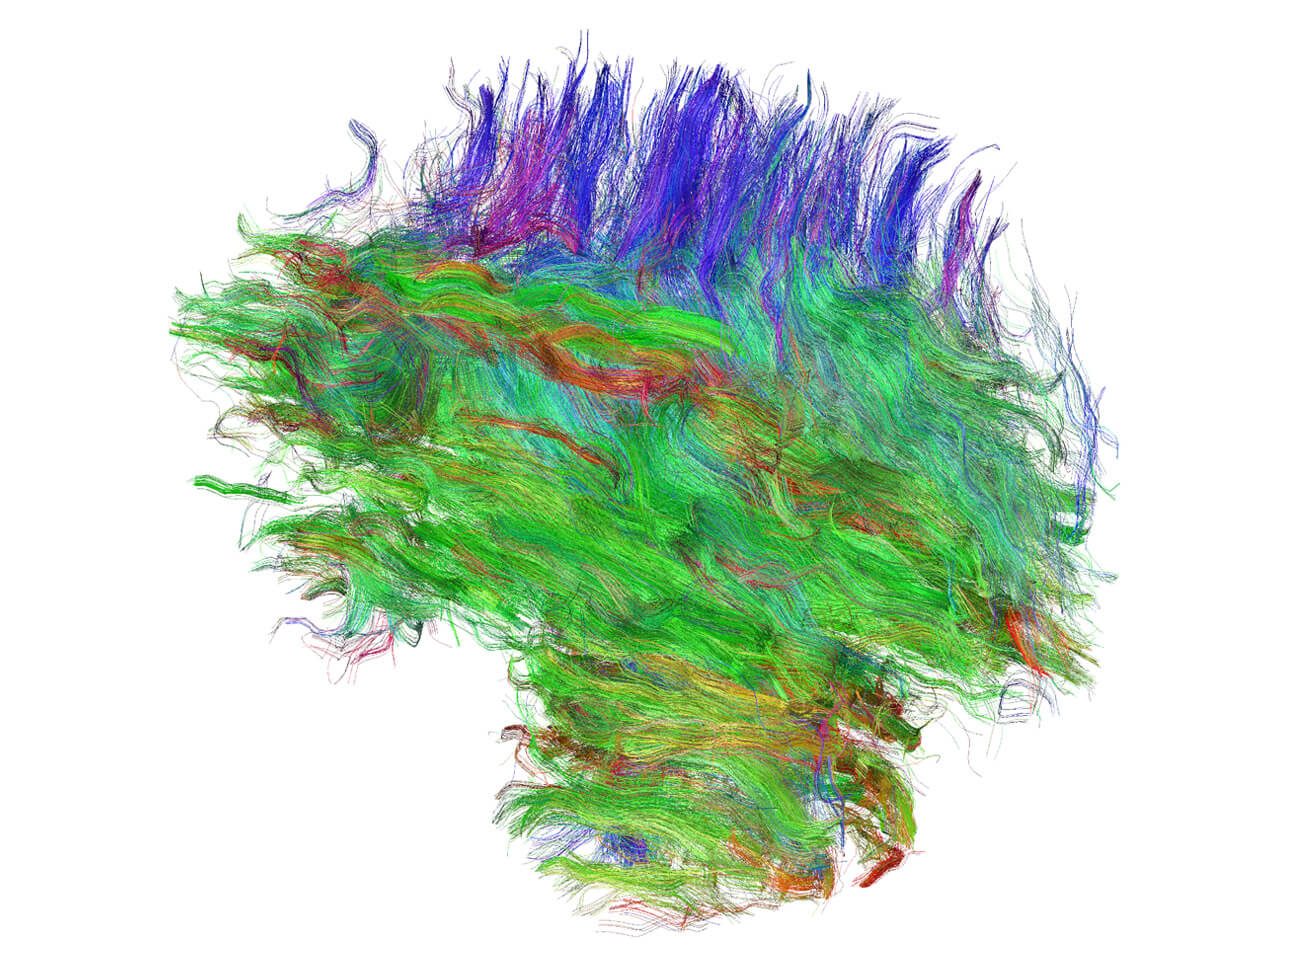

Most research in schizophrenia has been traditionally based on “wide” perspectives and there is an urgent need of circuit-based approaches, which focus on well-identified cerebral regions, their connectivity and their physiology. The thalamus is a very good candidate to perform this directed research, because schizophrenia is characterized by disturbances in both perceptual processing (e.g., hallucinations) and cognitive functions (e.g. impaired working memory), which likely reflect alterations in its structure and function and its connectivity with other cerebral regions, particularly with the neocortex. In fact, there is solid evidence from neuroimaging and postmortem data of alterations in the thalamus of patients with schizophrenia, but there are not multidisciplinary studies focused only on this region and integrating genetic, structural and functional data from clinical and preclinical sources. The general objective of this project is to study how adverse experiences during early life (childhood and adolescence) influence the thalamus, its circuits, the genes involved in their construction and their physiology, and whether these alterations can be predisposing factors for schizophrenia.

The project tackles its main objective using a multidisciplinary and translational approach. We will use animal models of adverse experiences using transgenic mice, combining molecular, structural and connectivity analyses with superresolution microscopy, behavioral tests and transcriptomics. The project also includes analyses of the thalamus of patients using postmortem tissue. Clinical studies will be also performed in living patients using psychological evaluations, expression analysis in blood and in olfactory neurons of genes relevant to thalamic function/plasticity and DNA methylation analysis of candidate genes. We also plan to generate IPSC cells from patients and, through a collaboration, generate thalamic organoids to study gene expression and connectivity. We will also analyze neuroimaging data in structural and functional MRI from patients to determine changes in different thalamic nuclei, as well as in their projecting regions in the cerebral cortex. Finally, we will perform correlation analyses of all neuroimaging, gene expression, epigenetic and organoid data. The project will be performed both in its basic and its clinical parts on males and females.